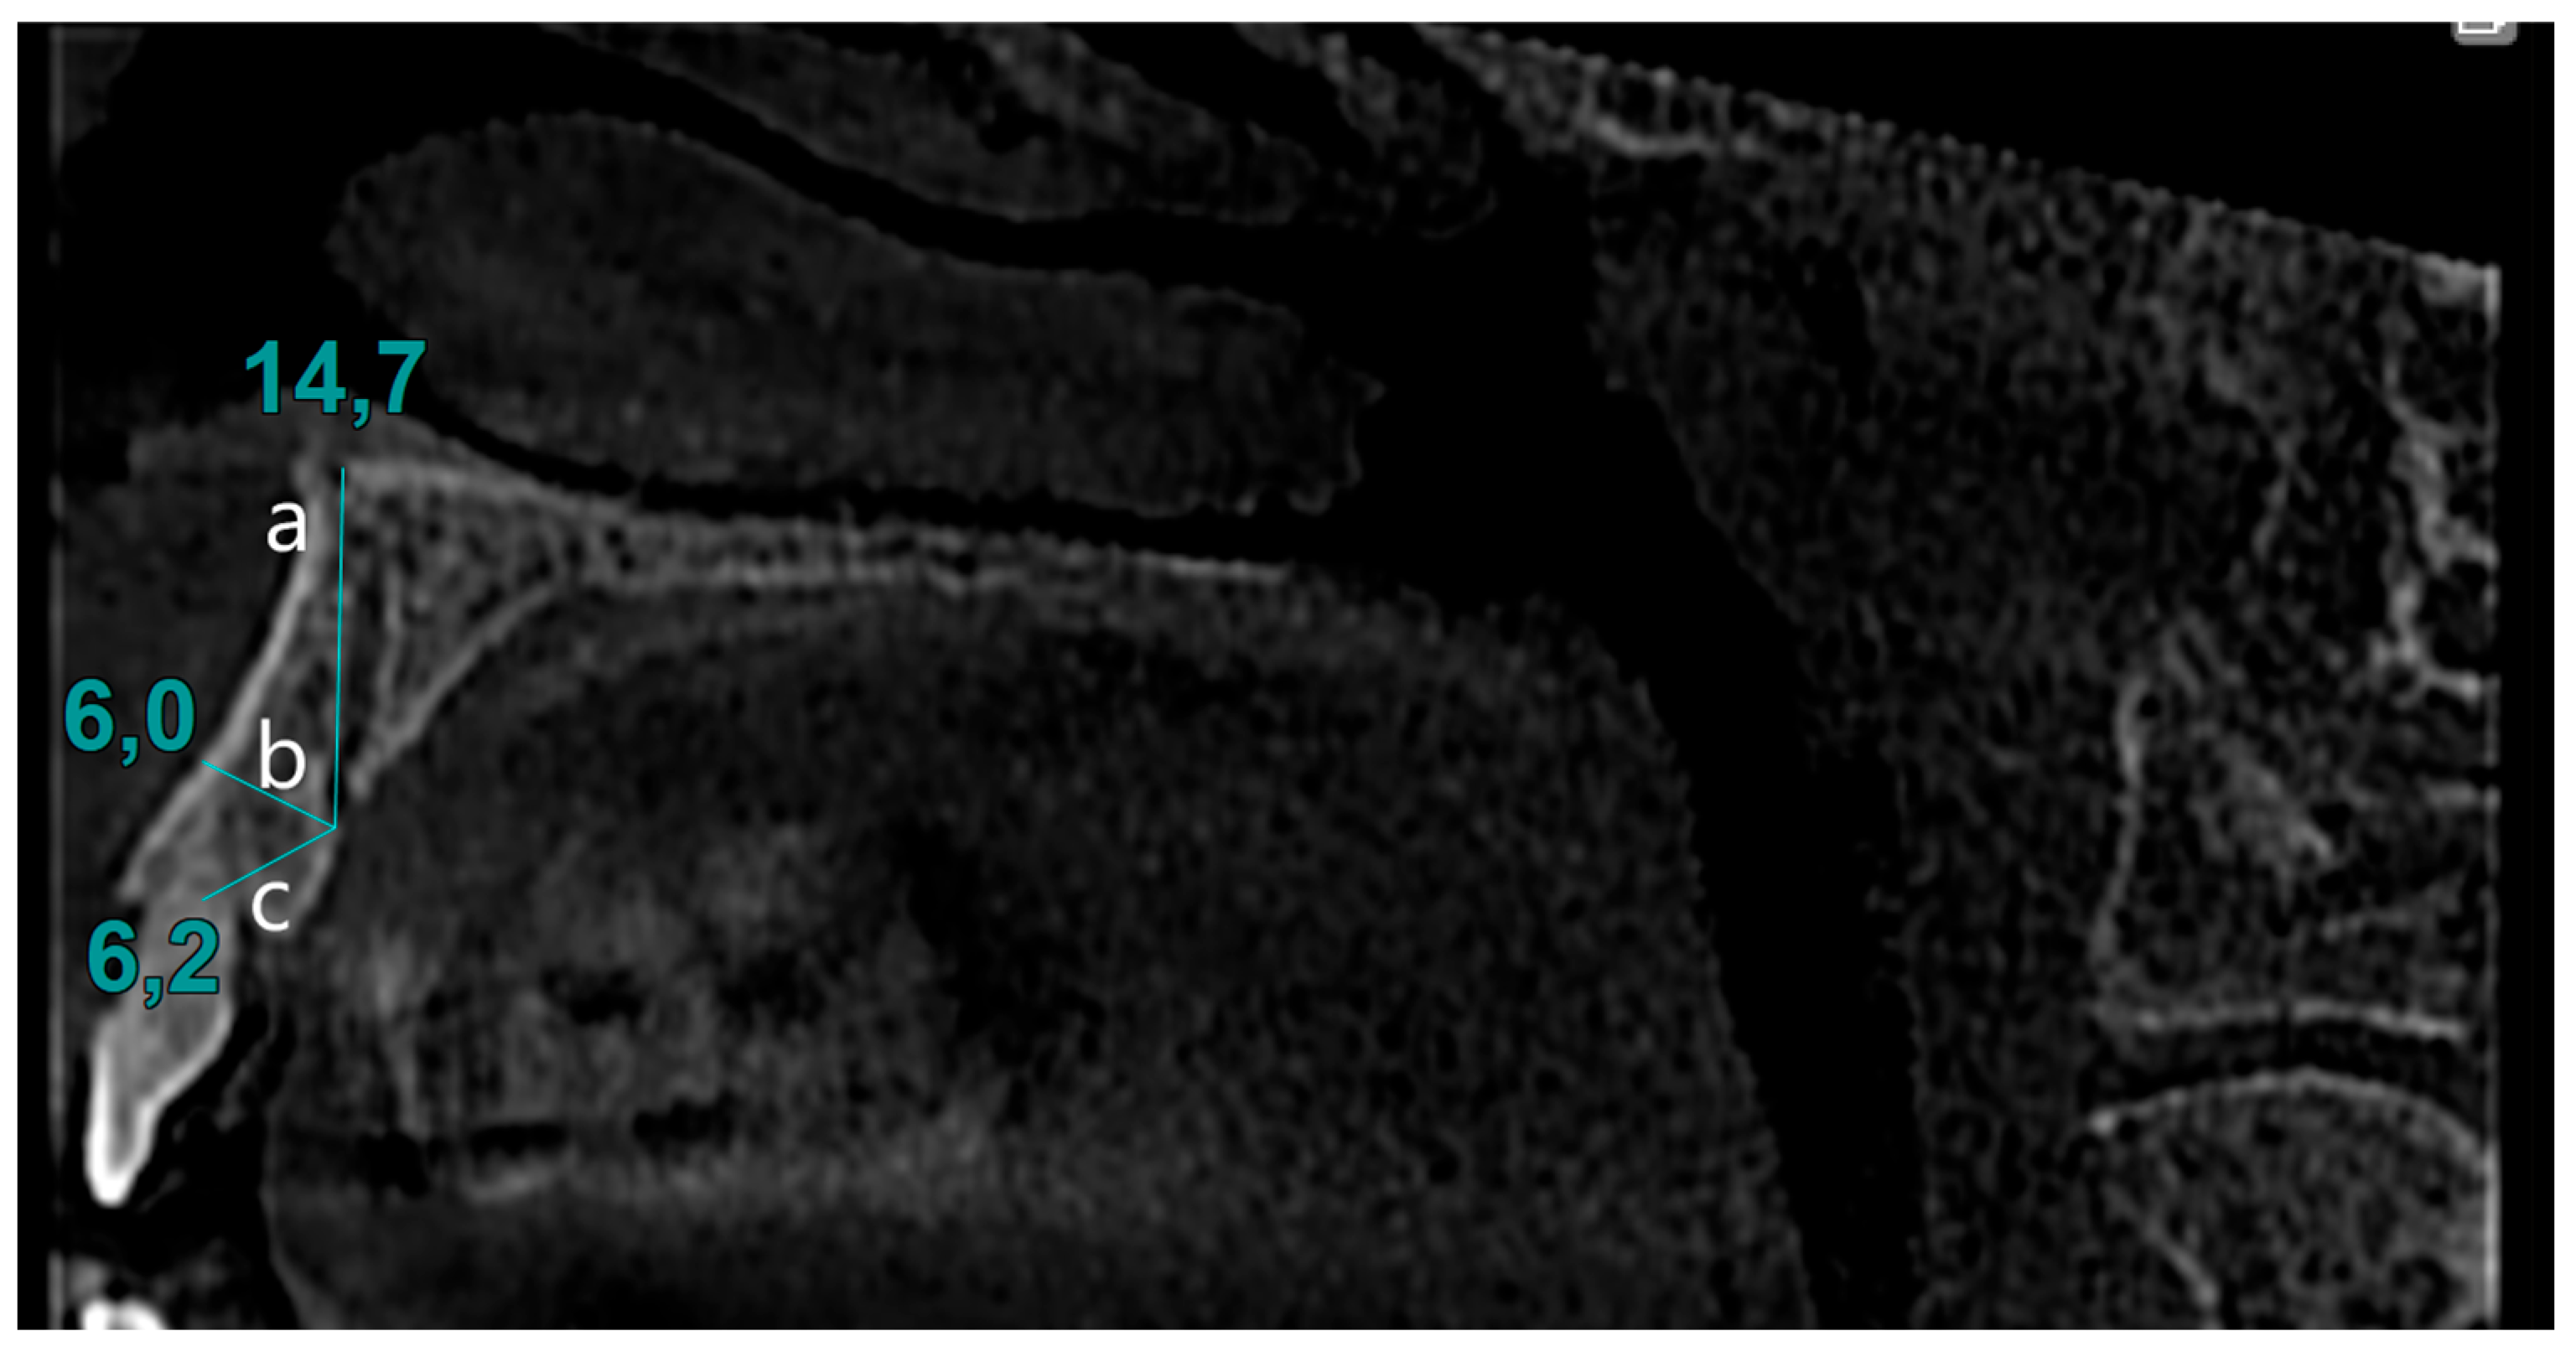

The presence of the CS in the sagittal section was identified. The identified images were verified in the transverse section. Diameters of CS were calculated by measuring the opening at the palatal cortical plate. The distance between the canal opening and the tangent line drawn to the nasal cavity floor was measured in the sagittal section. Similarly, the distance between the canal and the alveolar crest, as well as the distance between the buccal cortical bone and the CS, was determined using the same method (Figure 2).

Figure 2.

Evaluation of CS parameters: (a) distance to nasal cavity floor from CS, (b) distance to buccal bone from CS, (c) distance to alveolar crest from CS.